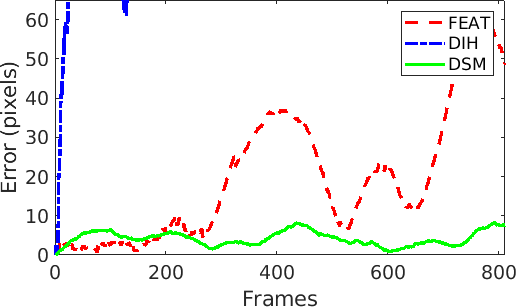

The visualization and comparison results on one circular loop (360 frames) of the SYN sequence are shown in Fig. 3(a)-(c). Note the small drift in DSM compared to FEAT. Similar behavior is observed from the mean residual error in Fig. 3(d) where the errors are reported for FEAT, DIH and DSM for the complete length of the sequence (811 frames). It can be seen that the error for FEAT starts increasing after approximately 300 frames and the mosaic starts drifting away. DIH error explodes within a few frames due to the random perturbation during training (Sec. 2). On the other hand, the error for DSM is very small and remains bounded. This is further verified from the low RMSE (0.36) and photometric (2.48) errors for DSM (Fig. 4). Comparison of our proposed DSM with FEAT and DIH is presented in Fig. 4. Overall the pairwise homography errors are high for FEAT for all five sequences due to poor visual quality and lack of texture in the fetoscopic videos. The RMSE and photometric errors for DIH are low compared to FEAT but are always higher compared to DSM (e.g. RMSE on EX for DIH (1.64) and DSM (0.38)). In DIH, this error accumulated over time during mosaic generation and resulted in a large drift. For EX, PHN1, PHN2 and INVI sequences, the average RMSE errors are 0.38, 0.32, 0.35 and 0.34, and photometric errors are 0.98, 1.76, 1.52, 2.42, respectively.